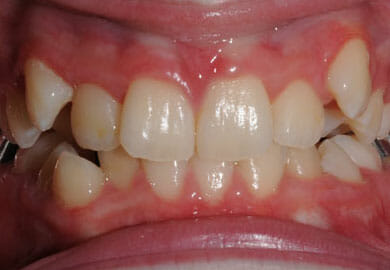

This lady hated her very uneven smile, all the teeth sticking out at the sides, teeth bunched together and uneven. We fitted clear brackets and a wire on the inside in the upper jaw in the roof of the mouth and in under 18 months the teeth were perfectly aligned and the patient’s smile was changed forever.